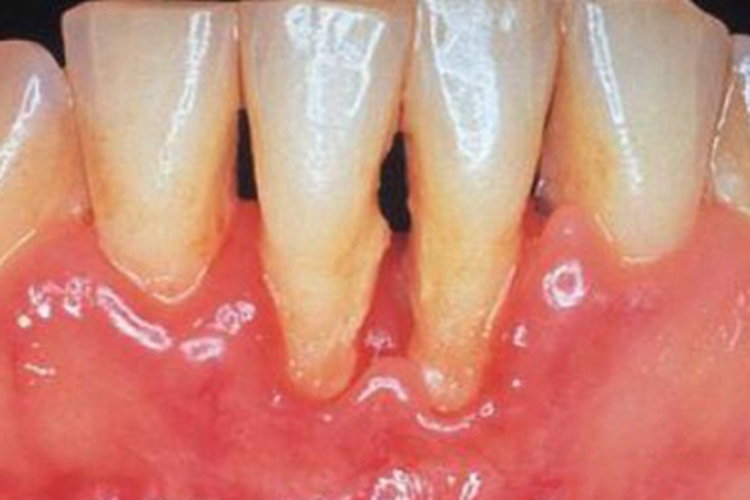

牙龈萎缩可导致牙龈出现不同程度的萎缩,外露出相对较细长的牙根、牙颈,导致牙缝增宽、变大,牙根表面发黄,可呈浅黄色、黄褐色。同时牙龈有异常的充血、红肿,可呈淡红色至鲜红色不等,质地坚韧,弹性减弱,触之易出血。

牙龈萎缩的发生多与刷牙不当(如刷毛过硬、牙膏粗糙、刷牙方式不正确等)、固定修复体位于龈下过深、牙周炎等有关。另外,牙齿的咬合力太大或者矫正牙齿时,牵拉牙齿移动的力量过大,也容易引起牙龈萎缩、红肿,导致细长的牙根、牙颈外露。